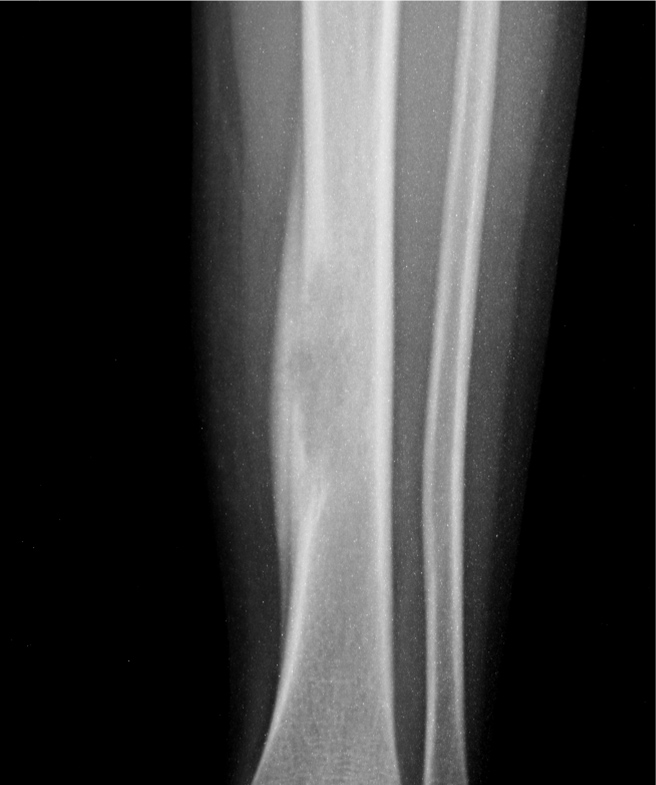

男孩,5岁,左小腿疼痛,肿胀,活动受限20天。

左胫骨中下段见一长卵圆形骨质破坏区,走形方向与胫骨长轴一致,边缘轻度硬化,内后侧骨皮质破坏,伴明显骨膜增生,破坏区内呈软组织密度。未见明显软组织肿块。

意见:左胫骨嗜酸性肉芽肿可能性大。

鉴别:本病主要与胫骨恶性肿瘤,尤其尤文氏瘤鉴别。后者骨质破坏范围更广、破坏区边缘往往不规则,骨膜增生更明显、骨膜增生可见较明显的骨质破坏,放射状骨针常见,多见软组织肿块。一般可以鉴别,当然确诊有赖于病理学检查。另外,与骨髓炎等鉴别不难。

左胫骨中下段见一不规则虫蚀样骨破坏,走形方向与胫骨长轴一致,边缘轻度硬化,伴明显骨膜增生,ct见破坏区内见磨玻璃样密度,其旁软组织钟胀,内见不规则钙化。

考虑:骨纤垩变可能性大,嗜酸性肉芽肿亦不除外.

左胫骨中下段见一不规则虫蚀样骨破坏,走形方向与胫骨长轴一致,边缘轻度硬化,伴明显规则的骨膜增生,ct见破坏区内见磨玻璃样密度,其旁软组织钟胀,内见不规则钙化。

考虑:嗜酸性肉芽肿。骨髓炎与尤文氏瘤待排

病史资料不完善,根据年龄、部位、及影像学表现,主要表现胫骨骨干囊性骨质破坏,骨皮质受累,局部骨膜反应,未见骨膜破坏及瘤骨,未见放射状骨针。 首先要考虑胫骨转移瘤,建议进一步检查,除外视网膜母细胞瘤,神经母细胞瘤,肾母细胞瘤,肾上腺等恶性肿瘤骨转移。排除转移瘤后考虑嗜酸性肉芽肿可能性大,患者年龄5岁,尤文氏瘤不太考虑,骨肉瘤也不太符合,骨髓炎待排,影像表现不太支持。建议进一步检查,除外原发恶性肿瘤胫骨转移后,考虑嗜酸性肉芽肿。必要时穿刺活检。